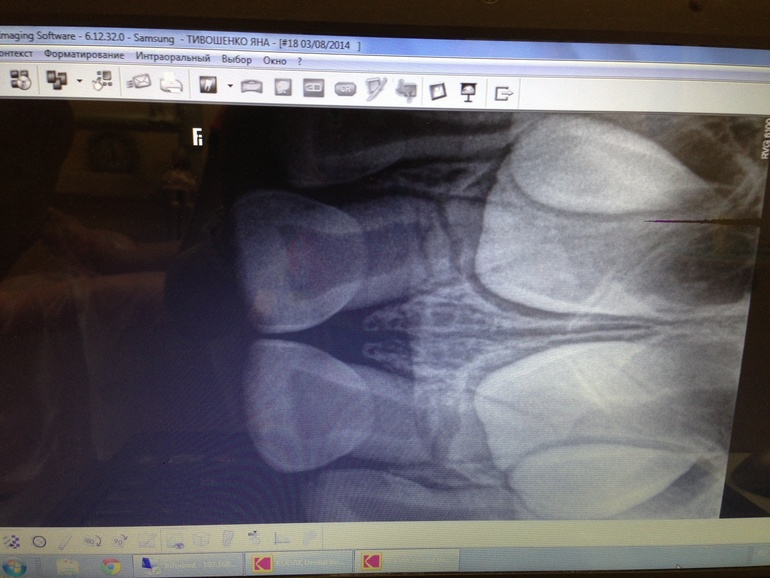

На ренгене видны трещины в обоих зубах. Зачатки не постадали(предварительно)